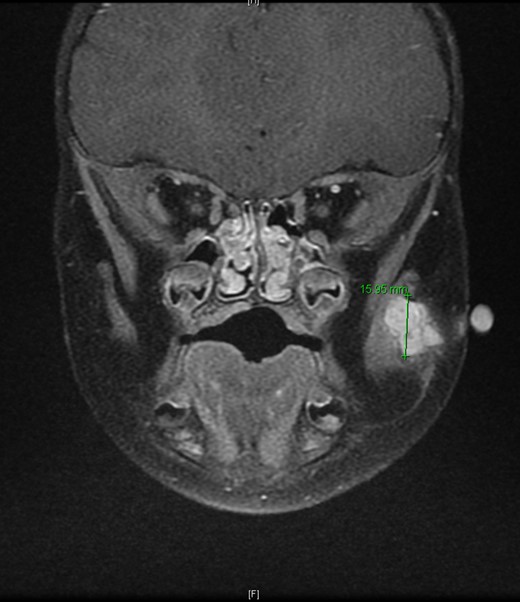

An 11-month-old male with a history of nasolacrimal duct stenosis and 4 mm thyroglossal duct cyst presented for evaluation of left facial swelling for 9 months. Approximately 6 months prior to admission, a mass was identified on the left cheek which had progressively increased in size over the past 2 months. The patient also had intermittent fevers the week prior to admission but was otherwise healthy. Baseline labs, including platelets, were within normal limits. On exam, he was found to have a firm, mobile, non-tender mass just inferior to the left zygomatic arch. Ultrasound revealed a vascularized solid lesion measuring 12 mm × 15 mm × 16 mm limited to the superficial soft tissues. MRI showed a multi-lobular mass with increased T2 signal centered within the left masseter and infiltrating signal in surrounding subcutaneous tissue (Fig. 1). The patient subsequently underwent ultrasound-guided core biopsy. The initial pathological diagnosis was consistent with TA, showing fibrovascular tissue containing compact nests of variably sized and ill-defined vascular channels. Immunohistochemistry staining showed the endothelial cells to be diffusively reactive for CD34 and CD31, partially reactive for D2-40, and negative for GLUT-1. However, upon further review, KHE was favored given the solid and infiltrative components on MRI, normal overlying skin on exam, and location of the lesion within subcutaneous fat. Accordingly, low-dose daily aspirin was prescribed prophylactically to prevent KMP. An MRI 2 months later, along with serial ultrasound images in the ensuing 26 months, showed no further growth (Fig. 2). His parents noted intermittent painless changes in size that did not seem to be related to any stimulus and returned to baseline size within hours. Surgical intervention at 3 years old is anticipated.

T2-weighted MRI 2 months later revealed a 14.5 mm × 14.1 mm × 15.95 mm mass partially involving the masseter muscle with no internal vascular flow voids.